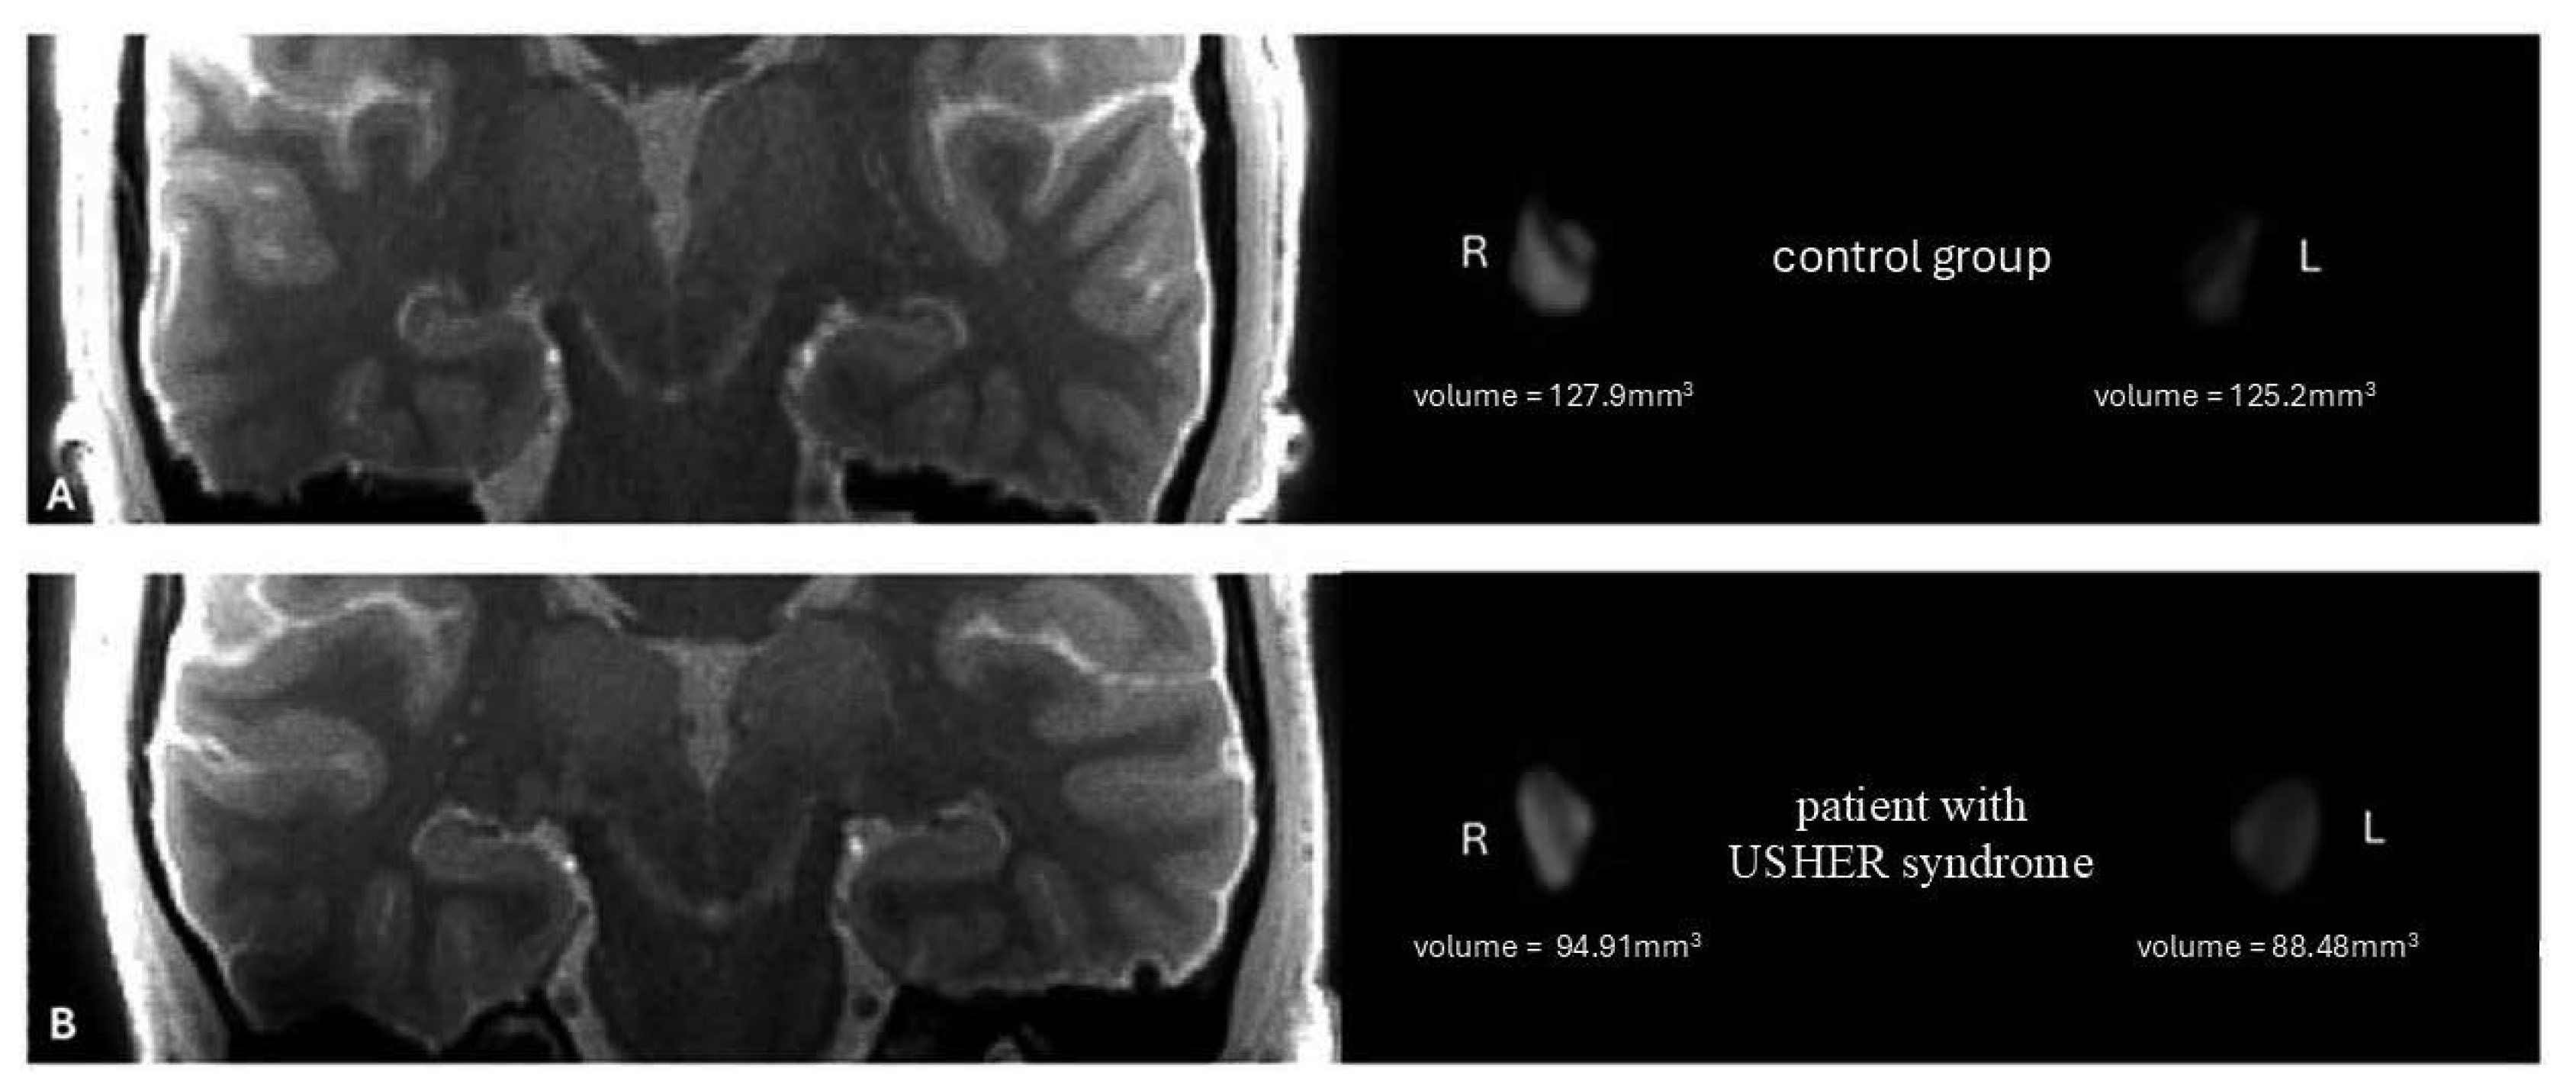

3. Results

Mean left (88.61 mm3) and right (95.65 mm3) LGN volumes are significantly lower in the USH group than in the control group (left 120.37 mm3, right 126.64 mm3) (t = 11.89; p < 0.001 and t = 11.86; p < 0.001, respectively) (Figure 1 and Figure 2).

Figure 3. On the left—the anatomical image of the brain 3D MT-weighted SILENT with marked LGNs; on the right—3D view results of LGNs manual segmentation using ITK-SNAP software. Images show one case chosen from the control group (A) and patients with Usher syndrome (B). Images acquired at the Ecotech Complex (Lublin, Poland).